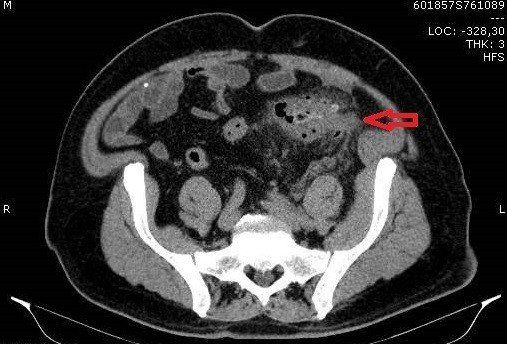

TC de abdome com contraste endovenoso fase excretora, evidenciando sinais de diverticulite aguda caracterizados por espessamento parietal do colon sigmoide, divertículos, densificação da gordura regional e presença de pequeno gás extraluminal, indicando pneumoperitônio discreto. Não há evidência de coleções pericolonicas associadas.

Na imagem, a diverticulite não complicada é caracterizada por filamento de gordura focal adjacente a um divertículo do cólon, geralmente o sigmóide. Uma pequena quantidade de líquido extraluminal e lóculos de gás podem estar presentes.

Encordoamento pericólico, muitas vezes desproporcionalmente proeminente em comparação com a quantidade de espessamento da parede intestinal

Espessamento segmentar da parede intestinal

Realce da parede do cólon

Perfuração diverticular

Extravasamento de gás e fluido para a pelve e cavidade peritoneal